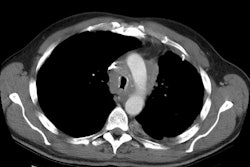

Shown below is an immune compromised patient with invasive pulmonary Aspergillosis infection. CT scan demonstrated an air crescent reflecting air between the infarcted, retracted lung and the adjacent normal lung parenchyma. This is a late finding in Aspergillosis infection.